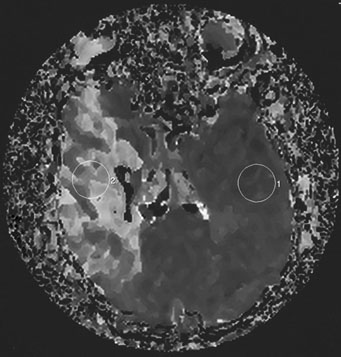

As diffusion-perfusion MRI and other techniques to quantify blood flow, such as perfusion CT and xenon-CT, become more widely available, clinicians will be better equipped to estimate the relative benefits and risks of thrombolysis, based more on physiologic data than rigid time constraints. Patients with large areas of penumbra tissue would benefit most, while those with large tissue volume with blood flow under 10 mL per 100 g/min would not benefit and may be at increased risk for hemorrhage. A recent report utilizing diffusion-perfusion MRI to guide thrombolysis with desmoteplase allowed the safe and apparently efficacious administration of this thrombolytic agent up to 9 hours after the onset of ischemia.45 Figure 1 exemplifies the use of diffusion-perfusion MRI in acute stroke treatment. Ideally, multimodal testing of the parenchyma to exclude hemorrhage, a viability study to determine the amount of salvageable brain, and a vascular study to assess vessel patency would provide the clinician with the information to make rational decisions regarding the need to treat. Magnetic resonance (MRI, diffusion-perfusion imaging, and magnetic resonance angiography [MRA]) and CT technology (with CT perfusion and CT angiography) have the potential to guide this multimodal evaluation.

Fig. 1. An 81-year-old man with atrial fibrillation developed acute onset of left-sided weakness and presented to hospital 3 hours and 40 minutes after onset of symptoms. A: The diffusion-sequence magnetic resonance imaging (MRI), with infracted tissue in the right basal ganglia in white. B: Decreased perfusion in the right middle cerebral artery distribution (white area). Given the relatively small diffusion abnormality and the large perfusion defect, it was decided to proceed with thrombolysis despite the time elapsed.